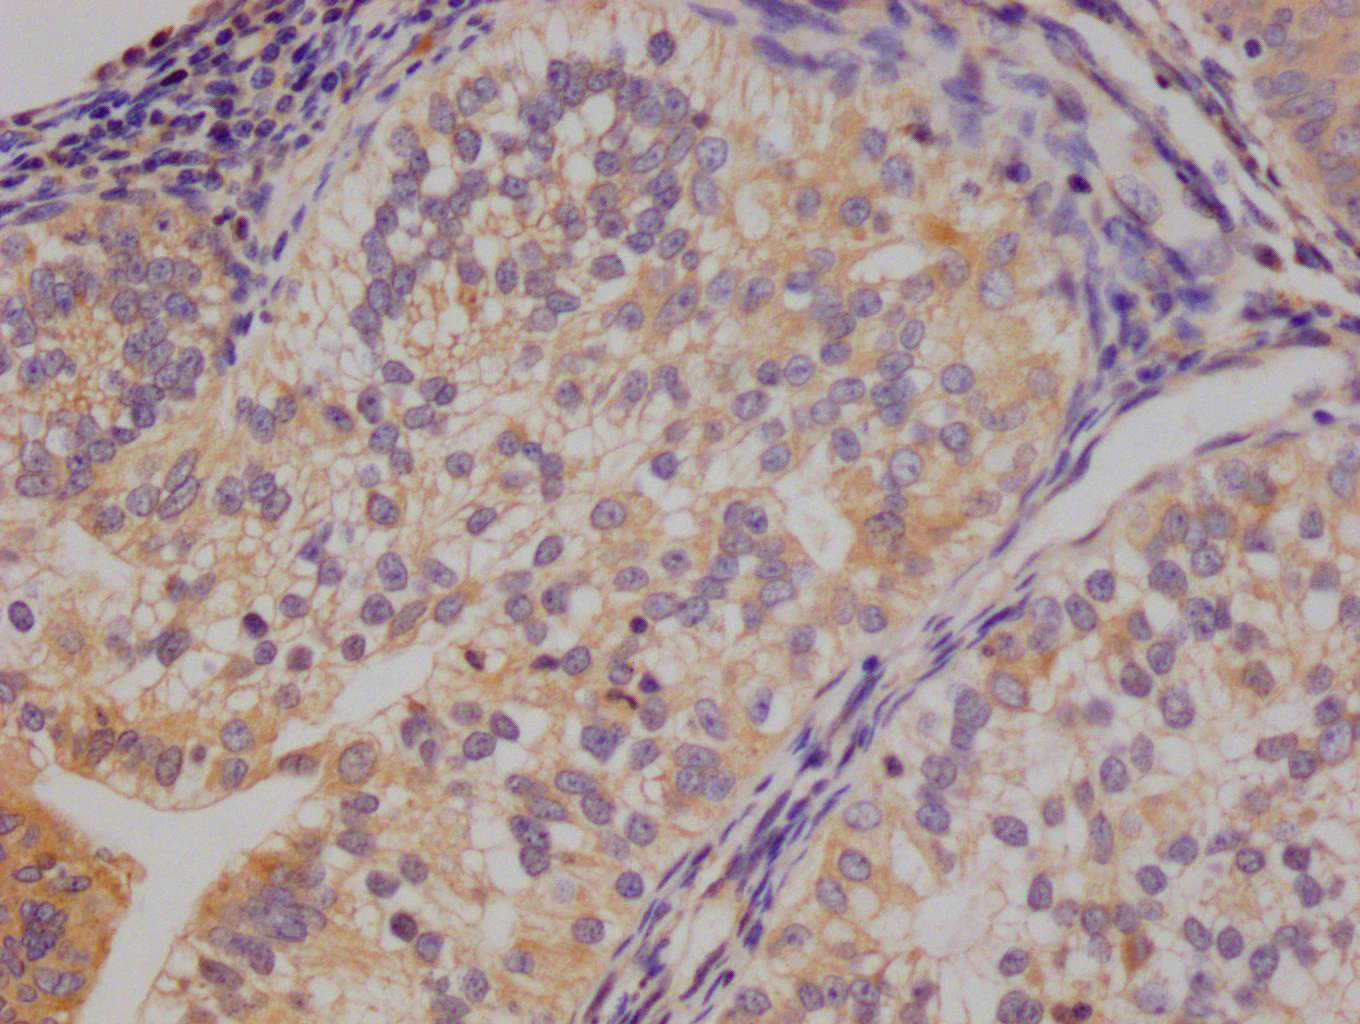

The image on the left is immunohistochemistry of paraffin-embedded Human thyroid cancer tissue using CSB-PA274333(DKK3 Antibody) at dilution 1/30, on the right is treated with fusion protein. (Original magnification: ×200)

The image on the left is immunohistochemistry of paraffin-embedded Human gastric cancer tissue using CSB-PA274333(DKK3 Antibody) at dilution 1/30, on the right is treated with fusion protein. (Original magnification: ×200)